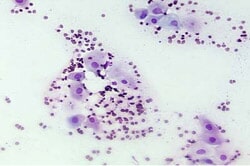

פרואסטרוס- מתחילת הדימום ועד לשלב הייחום הפעיל וקבלת הזכר, מתאפיין בדימום והתנפחות שפתי הבושת. הכלבה מושכת זכרים על ידי פרומונים המצויים בהפרשות הוגינאליות, השתן או השקים האנאליים לפי מחקרים שונים, אך לא תקבל זכר שינסה להרביעה בשלב זה (תסתובב, תתיישב או אף תתקוף). הפרואסטרוס קורה בהשפעת הורמון האסטרוגן ונמשך בממוצע כתשעה ימים. התא הדומיננטי הנראה במשטח שנלקח מהואגינה בשלב זה הוא תא הנקרא parabasal , וכן תאי דם אדומים רבים:

אסטרוס- ייחום כלבות פעיל, הכלבה מקבלת זכר ובמצב נורמלי תאפשר הרבעה. הבושת עדיין מוגדלת אך יש ירידה בנפיחות (ההגיון הביולוגי-כך יתאפשר הזיווג) וירידה בדימום. הביוץ מתרחש כ-2-3 ימים מתחילת שלה האסטרוס, וזמן ההרבעה האופטימלי הוא 2-4 ימים לאחר הביוץ. באסטרוס יש ירידה בהשפעת הורמון האסטרוגן ועלייה בהשפעת פרוגסטרון. התא הדומיננטי במשטח ואגינלי בשלב זה נקרא superficial או cornified:

דיאסטרוס- מתחיל עם הפסקת קבלת הזכר על ידי הכלבה. קורה בהשפעת הורמון הפרוגסטרון (מילולית: פרו=בעד, גסטרון=הריון. הורמון תומך הריון) אם נקלט הריון, זהו שלב הריון הכלבה, אך גם אם לא נקלט הריון, רמות הפרוגסטרון גבוהות בשלב זה ובהשפעתו יש התפתחות רקמת העטינים וייתכן אף ייצור חלב גם בכלבה הלא-הרה. נמשך כ 60 יום. התאים הדומיננטיים במשטח ואגינלי הם parabasal ו intermediate וכן תאי דם לבנים:

אנאסטרוס- התקופה השקטה במחזור פוריות הכלבה מבחינת התנהגות. באופן נורמלי הכלבה בשלב זה לא תמשוך זכרים ולא תקבל זכרים להזדווגות. הבושת קטנה והפרשות מעטות אם בכלל. מתחיל לאחר המלטה או ירידת ברמת הורמון הפרוגסטרון לרמה בסיסית. נמשך 3-5 חודשים ונחשב כפסק זמן בין ייחום כלבות. התא הדומיננטי הנראה במשטח וגינלי בשלב זה הוא parabasal.